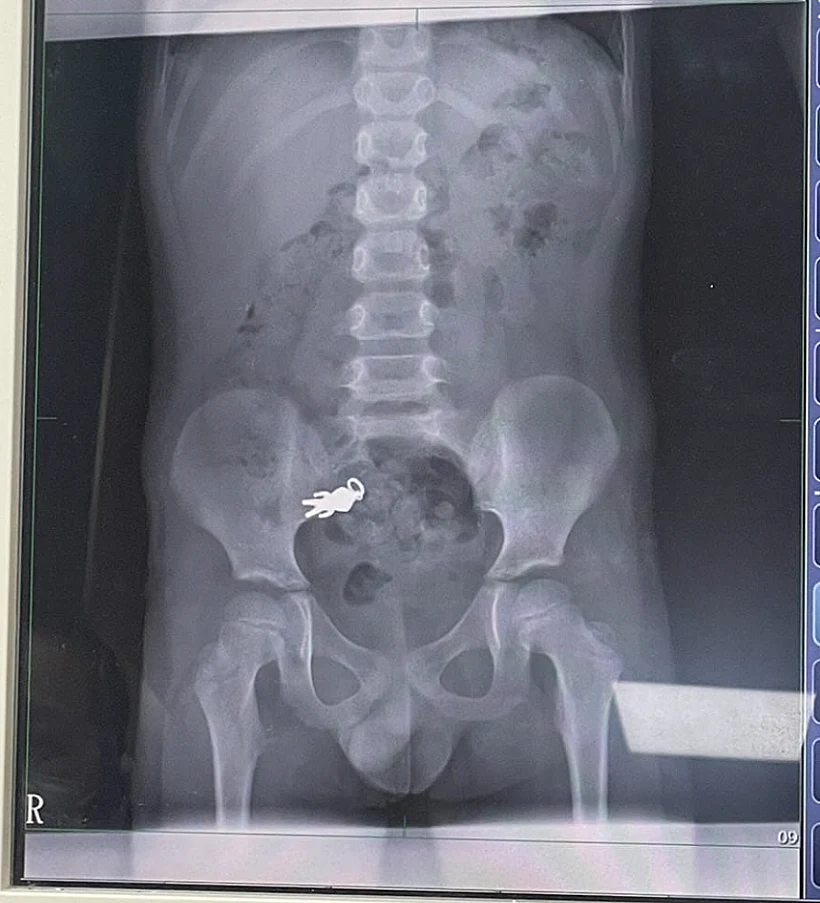

ילד בן שבע מטאיוואן פונה לבית החולים לאחר שבלע בטעות מחזיק מפתחות בצורת גיבור העל אולטרה מן. הרופאים קבעו כי אין צורך בניתוח מאחר והילד לא סבל מכאבים חזקים

הרופאים בבית החולים לואודונג בו-אי ערכו צילום רנטגן וגילו כי החפץ נתקע במעיים. ד"ר שיאה צ'ינטונג, שטיפל בילד, סבר כי מאחר ולא הופיעו סימנים של כאבים חריפים או חסימה, לא היה צורך בניתוח. הוא המליץ למשפחה להמשיך במעקב בבית, והזהיר כי הופעת כאבים חזקים, הקאות או עצירות ממושכת תחייב טיפול מיידי.

הצילום בו נראה מחזיק המפתחות בבירור, פורסם על ידי בני המשפחה ברשתות החברתיות ועורר תגובות רבות. גולשים רבים הגיבו בהומו על "מסע הגיבור" בתוך גופו של הילד. אחרים הביעו ביקורת כלפי ההורים על שלא השגיחו על ילדם.